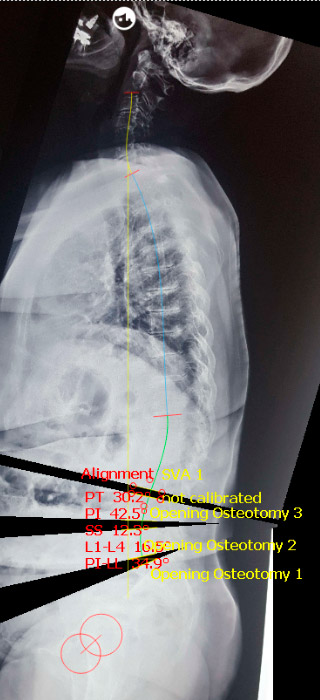

Utilizamos um programa computacional para estimar a correção, que deve neutralizar o balanço no plano sagital. Neste caso, aplicamos três osteotomias através de ALIF, estimando 1cm de abertura e 10 graus de lordose para cada segmento. Vejamos a correção estimada:

Fig. 6 – Pós-op (balanço neutro)